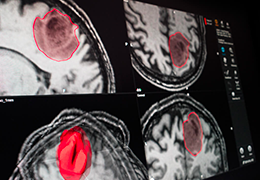

Statistical Analysis

BrainVoyager performs a wide range of statistical analyses including; parametrical mapping, contribution maps, Independent Component Analysis (ICA), Region-of-interest analysis and Event-related fMRI analysis. specifications.

Visualization Tools

Parametric and non-parametric statistical maps may be superimposed both on the original functional scans as well as onto T1-weighted 2D or 3D anatomical reference scans. Time courses of selected regions-of-interest (ROIs) are available both in 2D and 3D representations. Statistical maps may be computed either in the 2D or 3D representation since structural as well as functional 4D data (space x time) are transformed into Talairach space. This allows you to compare activated brain regions across different experiments and across different subjects

Segmentation of tissue (e.g., isolating the brain, differentiating gray and white matter) is performed using region-growing methods, filter operations as well as the application of 3D templates. Using the mouse it is very easy to explore a 3D volume with superimposed pseudocolor-coded statistical maps in a four-window representation showing a sagittal, coronal, transversal and oblique section. Based on a (segmented) 3D data set a three-dimensional reconstruction of the subjects' head and brain can be calculated and displayed from any specified viewpoint using volume or surface rendering.